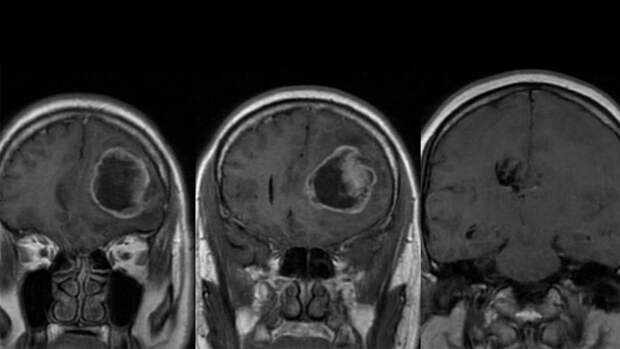

Ученые Дальневосточного федерального университета (ДВФУ) и дальневосточного отделения РАН разработали инновационный подход диагностики опухолей головного мозга на атомно-силовом микроскопе (АСМ). Об этом "Газете.Ru" рассказали в пресс-службе программы Минобрнауки "Приоритет 2030".

С его помощью специалисты могут одновременно изучать строение и механические свойства опухоли за 40 минут, классифицировать ее тип и агрессивность, что необходимо для срочной диагностики.

По словам ученых, такой подход открыт впервые в мире."Провести биопсию опухоли мозга без хирургического вмешательства невозможно, однако ее результаты могут быть критически важны для определения дальнейшего лечения. Наш метод позволяет провести диагностику за 40 минут во время операции по взятию материала для биопсии, в то время как классический метод требует две недели. Это позволяет принять решение по ее удалению уже во время первой операции, чтобы не затягивать процесс, если опухоль прогрессирует", – рассказал "Газете.Ru" сотрудник Лаборатории биомедицинских клеточных технологий ДВФУ Владислав Фарниев.